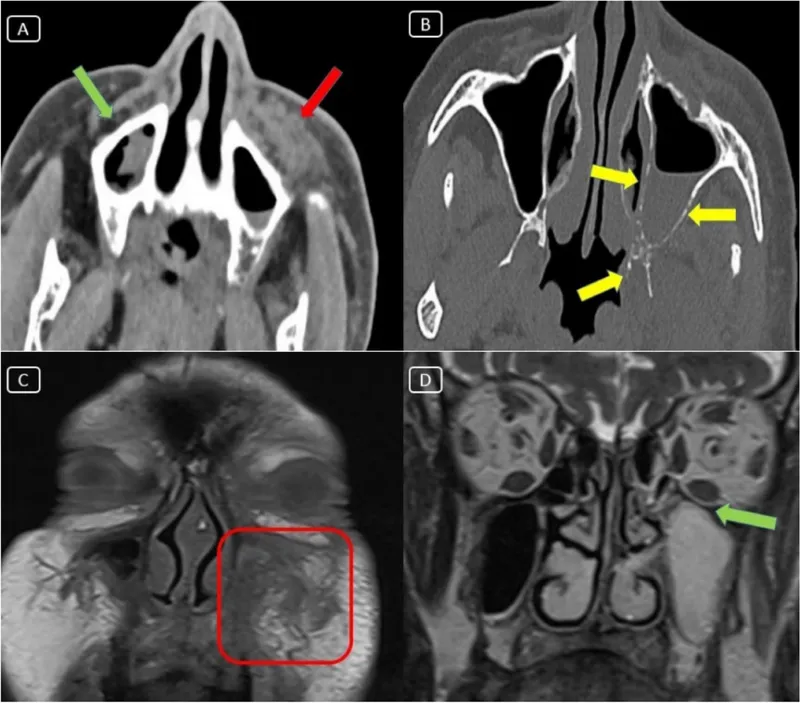

The sinus-orbital relationship explains 75% of orbital infections, with ethmoid sinusitis causing 85% of pediatric cases and sphenoid sinusitis producing orbital apex syndrome in 8% of adult cases. Understanding these anatomical pathways predicts infection severity and complications.

⭐ Clinical Pearl: The orbital apex syndrome from sphenoid sinusitis presents with complete ophthalmoplegia + vision loss + V1 numbness in 8% of invasive fungal infections. Mucormycosis shows black eschar in 60% of cases and requires immediate surgical debridement plus amphotericin B to prevent 25% mortality rate.

⭐ Clinical Pearl: Mucormycosis shows black nasal eschar in 60% of cases, ketoacidosis in 80% of diabetic patients, and rapid progression with orbital apex involvement within 48-72 hours. Mortality reaches 25% without immediate surgical debridement plus amphotericin B 5mg/kg/day.